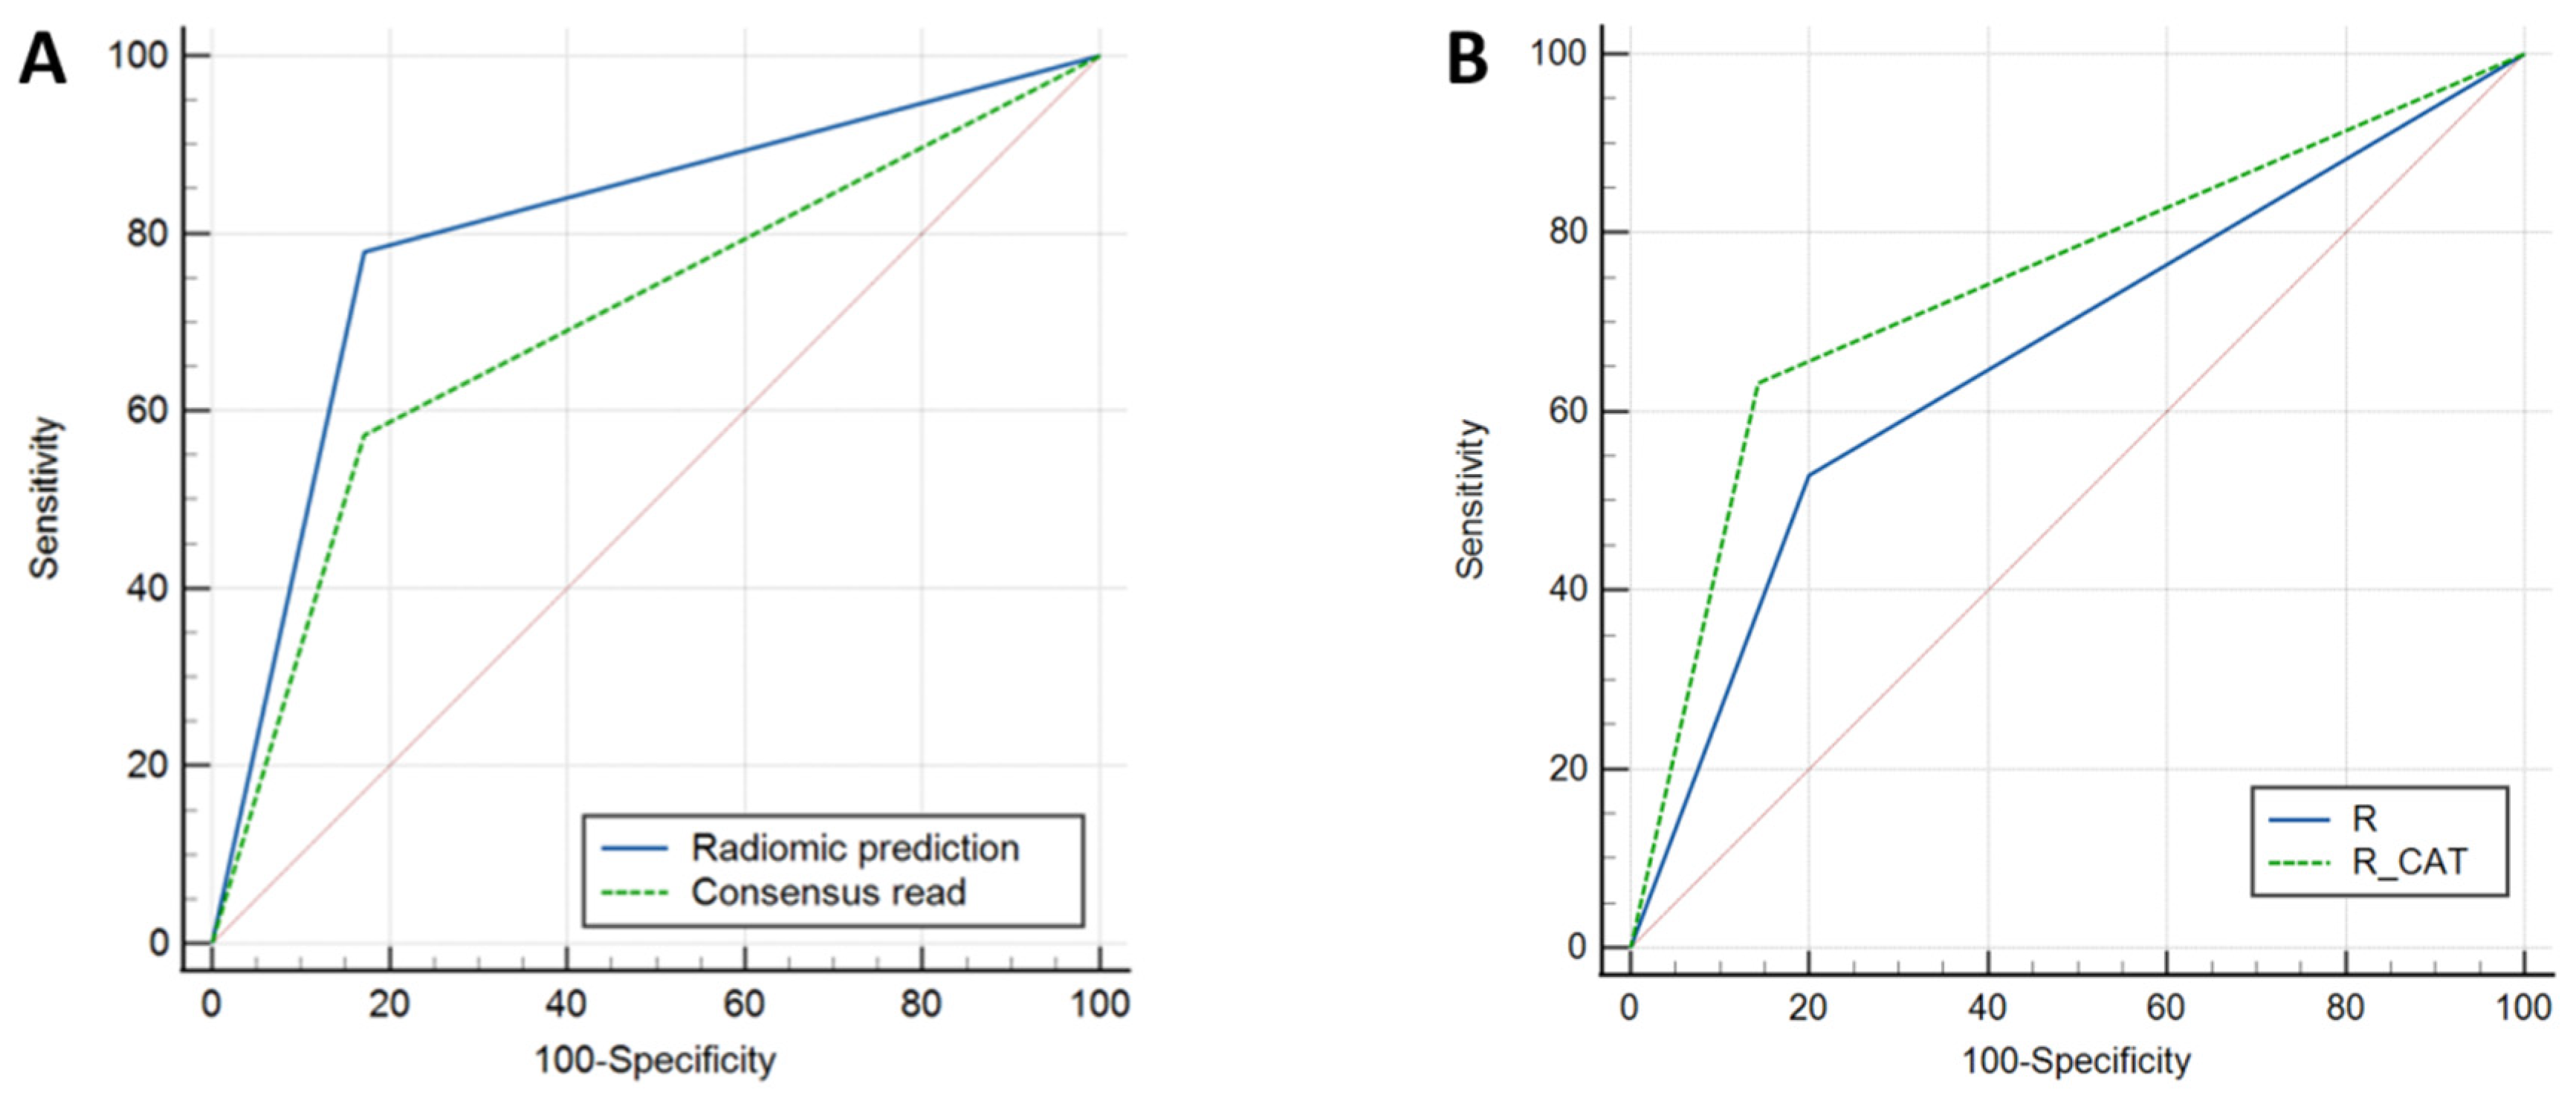

3.2. T2-FLAIR-Mismatch-Based Prediction of 1p/19q Co-Deletion Status

3.3. Radiomic-Based Prediction of 1p/19q Co-Deletion Status

3.4. External Validation Results

3.5. Neuroradiologist + Radiomics